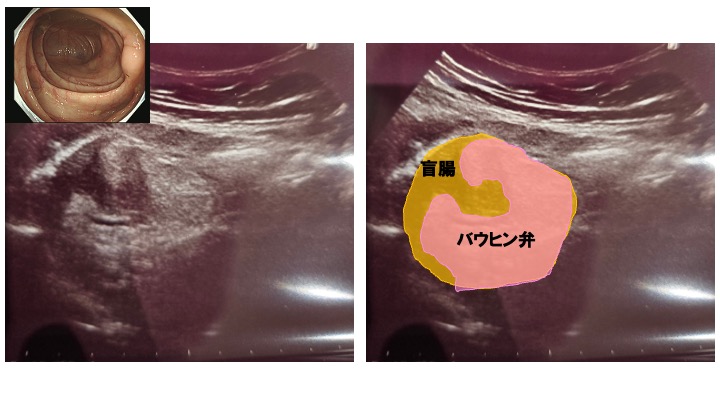

右下腹部には、プロラプス バウヒン(バウヒン弁は時に大腸に突出しています)を認めます。

今回の症例は、8mmと腫大を認めますが、周囲の脂肪組織に炎症の波及はなく、発症初期と考えられます。